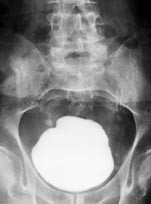

Steinen bestod hovedsakelig av kalsiumoksalat, veide 660 g, opptok et volum på 300 ml målt ved væskefortrengning og målte 9,6 ⋅ 8,5 ⋅ 7,2 cm3 (fig 2).